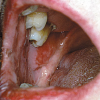

– Üle poolte haigusjuhtudest algab suus esinevate, kiiresti purunevate villidega. Villid on läbipaistvad

ja pehmed ning piirduvad algul, mõne kuu jooksul, ainult ühe piirkonnaga ja levivad seejärel üle kogu naha. Tervena näiv nahk villi ümber irdub sõrmega vajutades (Nikolsky sümptom).

Suu limaskestal tekivad valulikud erosioonid eelkõige nendes kohtades, mis traumeeruvad toidu

mälumisel ja neelamisel. Tihti on need pemphigus vulgarise puhul esmaseks haiguse väljenduseks. Epiteeli siseselt moodustub kahvatu vill, mis on väga õrn ja peale selle lõhkemist

jääb ebakorrapärase kujuga erosioon. Erosioon on väga pindmine, mistõttu puudub fibrinoosne

katt. Huultel võivad olla koorikud.